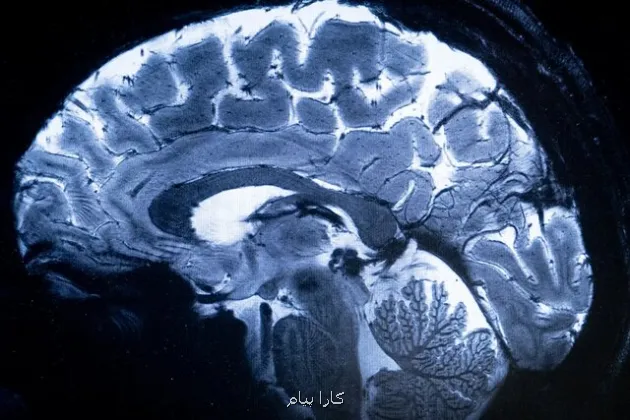

کارا پیام: چهاردهمین کنگره علوم اعصاب پایه و بالینی با حمایت ستاد توسعه علوم و فناوری های شناختی از 19 آذر در تهران گشایش می یابد. معرفی آخرین نتایج علوم اعصاب با حمایت ستاد علوم شناختی به گزارش کارا پیام به نقل از ایسنا، چهاردهمین کنگره علوم اعصاب پایه و بالینی بمنظور توسعه کارهای پژوهشی، تبادل آخرین دستاوردها و نتایج تحقیقاتی و نیز گسترش تعامل و همکاری میان پژوهشگران، متخصصان و محققان با حمایت ستاد توسعه علوم و فناوری های شناختی از ۱۹ تا ۲۱ آذرماه در محل مرکز همایش های بین المللی رازی دانشگاه علوم پزشکی ایران برگزار می گردد.

این کنگره با تأکید بر "پزشکی شخصی سازی شده"، فرصت مناسبی را برای پژوهشگران، پزشکان، دانشجویان و متخصصان فعال در حوزه علوم اعصاب پایه و بالینی فراهم می سازد تا در محیطی پویا به بحث و تبادل نظر، انتقال تجربه و اندیشه ورزی بپردازند و از این رهگذر پیوند بین تحقیقات علوم پایه و کاربردهای بالینی را در فضایی بین رشته ای تقویت نمایند.

ارایه تازه ترین موفقیتهای علمی و نتایج تحقیقاتی با حضور متخصصان برجسته داخلی و بین المللی در تمامی رشته های مرتبط از مهندسی تا پزشکی و علوم انسانی از رویکرد های این گردهمایی تخصصی به حساب می آید.